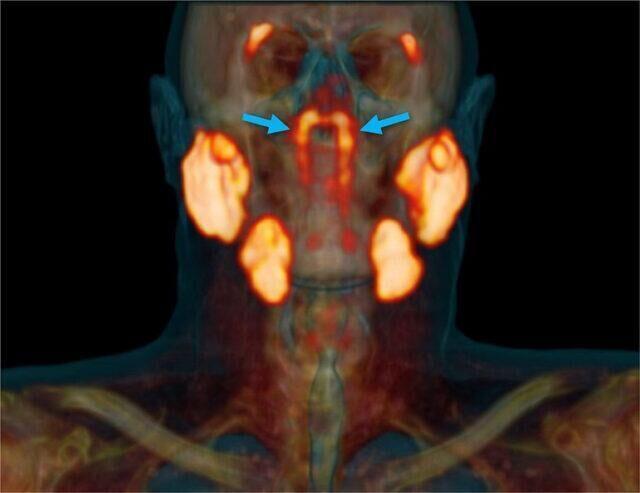

Seeking to learn more about cancer processes in the head and neck, researchers used scans with radioactive glucose which “highlighted” certain areas of the body.

They made use of positron emission tomography and computed tomography scans.

The oncologists scanned around 100 patients and cadavers and to their surprise, certain area of the face continued to glow. At first they decided that it was some kind of anomaly, but further investigation revealed that they were dealing with a whole new part of the human body.

The tubarial glands take part in the production of saliva within the mouth. The new organ is roughly the same size as the three main salivary glands. However, they are located on either side of the nasopharynx.